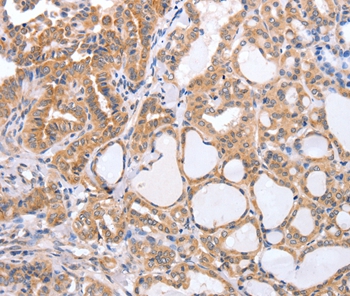

Immunohistochemical analysis of paraffin-embedded Human colon cancer tissue using #35957 at dilution 1/60.

Immunohistochemical analysis of paraffin-embedded Human thyroid cancer tissue using #35957 at dilution 1/60.